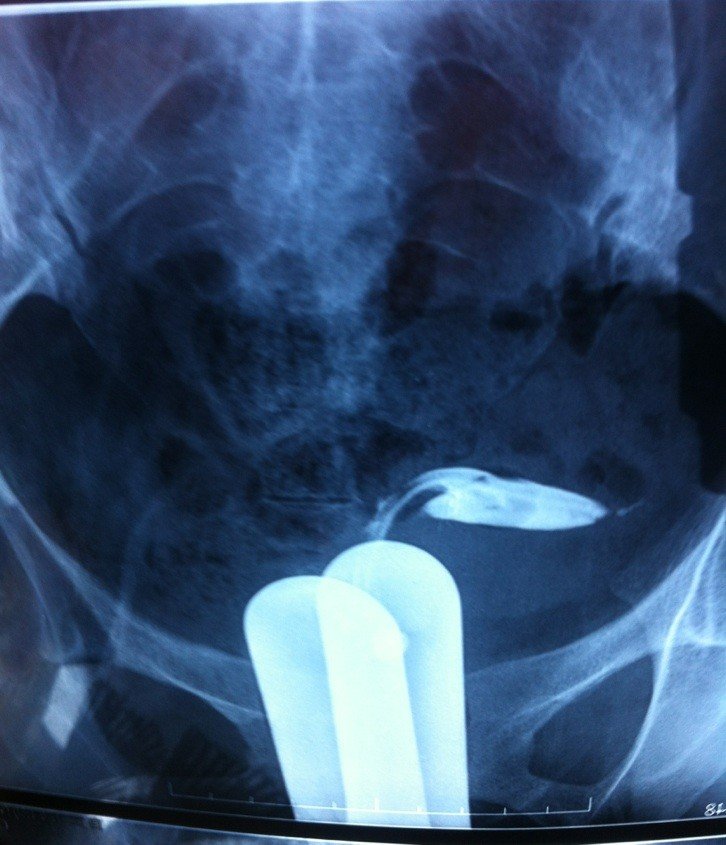

请问这种情况有多少机率自然受孕? 片子是输卵管造影术 点击展开 匿名用户 2013-12-06 17:29 为您推荐: 其他回答 只有一侧显影,机会剩一半!还有一张延时片吗?20分钟后看弥散情况的,如果弥散在盆腔里的碘油很多就说明通畅性不错,有机会怀孕。建议做个宫腹腔镜手术后检查和修复后,在月经第十天开始卵泡监测直到怀孕! 盖翠丝_APB7 2013-12-06 21:54 相关问题 请教!这种情况不知受孕的机率有多高 谢谢! 请问我15号来的月经,21号结束,25好和老公同房,我想问一下受孕的机率是多少 就是说月经前几天同房,后来有来过月经,这样可以怀孕吗,像这样的受孕机率有多少